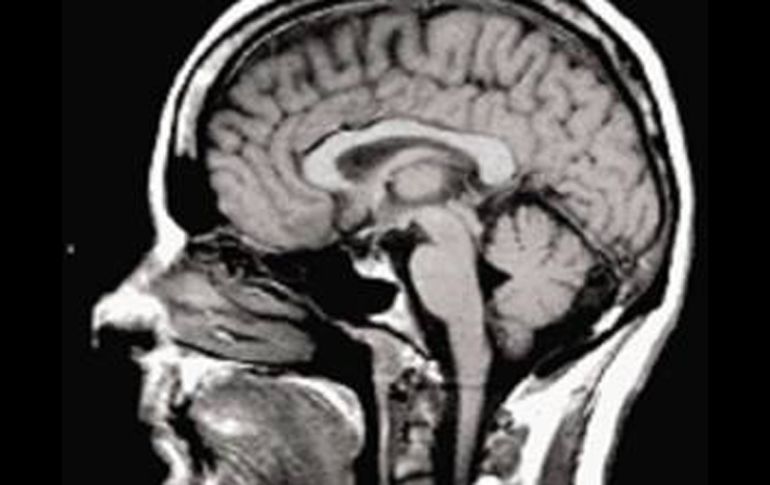

Tecnología | No se usan las mismas partes del cerebro al comunicarse en distintos idiomas Lenguas usan distintas partes del cerebro Un equipo de neurólogos chinos comparó las funciones neuronales de 15 extranjeros al hablar con las de un grupo similar de chinos Por: EFE 14 de octubre de 2010 - 16:04 hs Algunas palabras excitan las mismas partes del cerebro; otras actúan de manera diferente entre el chino y el inglés. EL UNIVERSAL / MADRID, ESPAÑA (14/OCT/2010).- Los hablantes de diferentes idiomas no usan las mismas partes del cerebro al comunicarse, según un estudio de un equipo de neurólogos chinos de cuyo resultado informa hoy el diario oficial Global Times. Los expertos compararon las funciones neuronales de 15 extranjeros al hablar y las compararon con un grupo similar de chinos. Aunque algunas palabras excitan las mismas partes del cerebro (por ejemplo, los equivalentes en diferentes idiomas a "papá" o "mamá"), otros vocablos actúan de manera diferente entre el chino y el inglés (entre ellos, otros parentescos como "hermano" o "tío"), destacó el estudio. La investigación, realizada por la Universidad Pedagógica de Beijing, se encuentra en su fase preliminar y podría arrojar nuevas conclusiones, destaca el diario. Otro estudio publicado en 2003 por la organización británica Welcome Trust defendía una gran diferencia entre los hablantes del idioma chino y los de las lenguas occidentales. Esta investigación señalaba que cuando una persona cuya lengua materna es el inglés escucha unas palabras en su idioma se activa su lóbulo temporal izquierdo, mientras que un chino "trabaja" también con el lóbulo derecho, que se activa cuando una persona oye música, debido al carácter tonal del mandarín (el tono musical de una palabra influye en su significado). Temas Investigación científica Ciencia médica Expertos del lenguaje Neurología Lee También INAPAM: ¿Cómo solicitar un turno para consulta médica gratuita? Investigación de Rancho Izaguirre no está archivada; 12 funcionarios están involucrados Nobel de Química premia el desarrollo de estructuras metal-orgánicas Nobel de Física para Clarke, Devoret y Martinis por descubrimiento sobre fenómenos cuánticos Recibe las últimas noticias en tu e-mail Todo lo que necesitas saber para comenzar tu día Registrarse implica aceptar los Términos y Condiciones